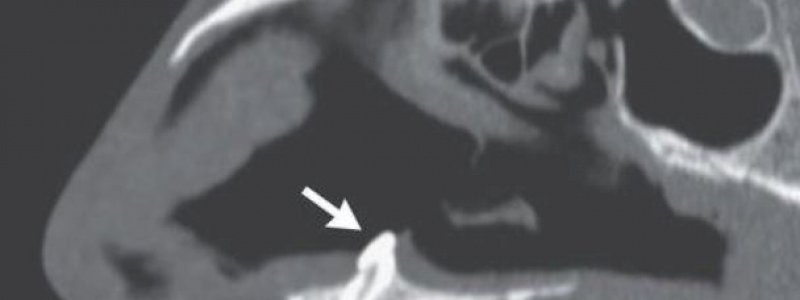

Dokter mencabut gigi tanpa komplikasi dan pria itu melaporkan selama kunjungan tindak lanjut tiga bulan setelah prosedur bahwa ia dapat bernapas normal melalui kedua lubang hidung.